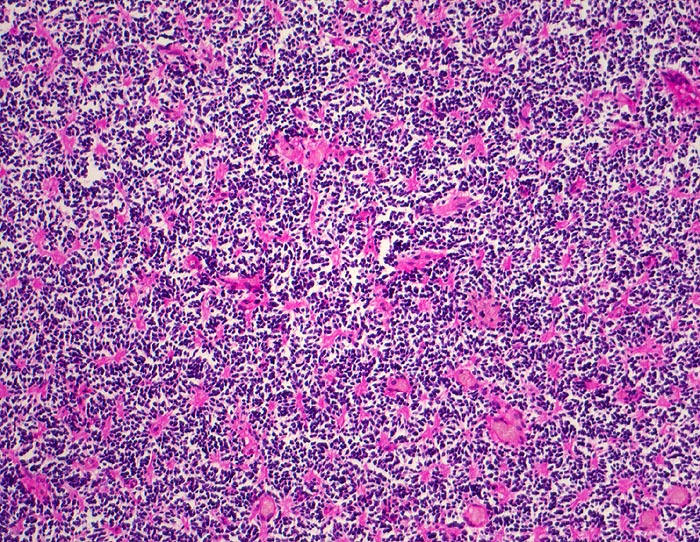

Wegen der hohen Zelldichte und der hohen Kern-Zytoplasmarelation erscheinen die Tumoren in der HE Färbung blau. Medulloblastome müssen differentialdiagnostisch von morphologisch ähnlichen kleinzelligen undifferenzierten Karzinomen und Lymphomen abgegrenzt werden. Das klassische Medulloblastom besteht aus dicht gepackten Zellen mit runden bis ovalen oder karottenförmigen stark hyperchromatischen Kernen umgeben von wenig Zytoplasma. Runde Zellen mit weniger dichtem Chromatin sind oft beigemischt. Zahlreiche Mitosen, flächenhafte Nekrosen und Apoptosen sind typisch. In weniger als einem Drittel der Fälle findet man die typischen Homer-Wright Rosetten. Diese bestehen aus ringförmig angeordneten Tumorzellkernen um ein fibrilläres Zentrum aus Zytoplasmafortsätzen.

• Scharf begrenzter rundlicher sehr zellreicher (deshalb blauer) Tumor.

• Monomorpher Zellrasen mit hyperchromatischen ovalen oder karottenförmigen Zellkernen.

• Kaum erkennbares Zytoplasma.

• Homer-Wright Rosetten aus ringförmig angeordneten Tumorzellkernen um ein fibrilläres Zentrum aus Zytoplasmafortsätzen.